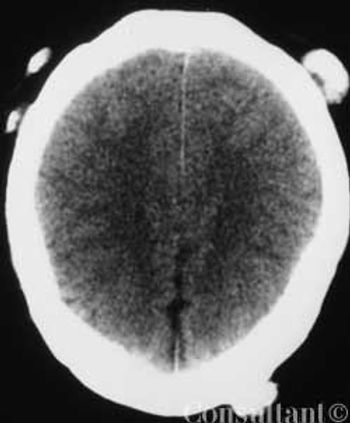

A 34-year-old white woman presentswith a 4-month history of diarrhea,with bulky, foul-smelling stools; flatulence;diffuse abdominal discomfort;and episodic nausea and vomiting. Shehas lost 13.5 kg (30 lb) during this period.The patient has had no fever, andher medical, family, and travel historyare unremarkable.